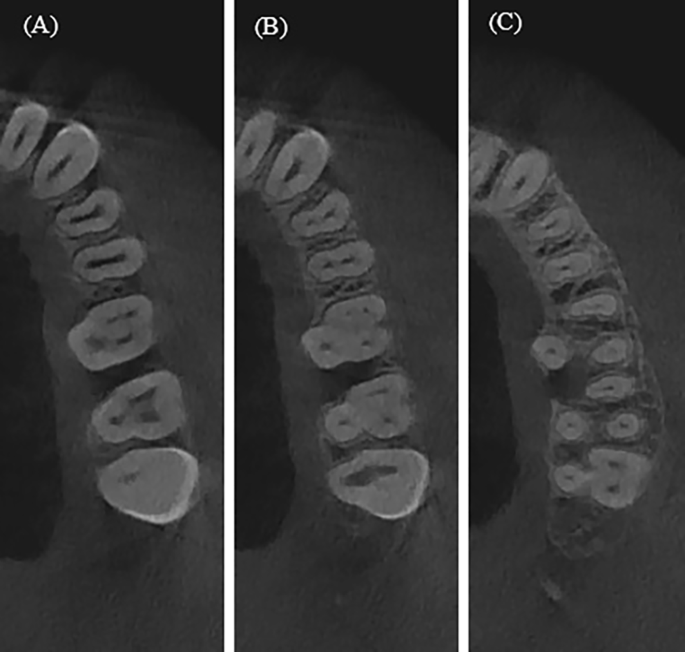

The study of root canal shape at the coronal, middle and apical parts showed that the shape is not constant; it changes depending on the number of canals in the root, the presence or absence of isthmuses. When analysing the maxillary anterior teeth, it was found that the shape of the central and lateral incisors in the upper jaw in 100% is round throughout its entire length (Table 1). The canines of the upper jaw and low jaw are characterized by an oval shape in 100%, which is preserved throughout its entire length (Table 1; Fig. 1). An analysis of the root canal shape of maxillary first and second two-rooted pre-molar showed that in the coronal third round shape was in 37.7% of cases, and oval in 62.3%. In the single-rooted maxillary premolars, in the coronal third, an oval shape, a ribbon-like type 1 and ribbon-like type 5 were revealed. In the middle and apical thirds, the ribbon-like type 1 changes into ribbon-like type 5 (Table 2; Figs. 1 and 2). In the maxillary molars, In MB in the coronal and middle thirds, a ribbon-like type 1 was detected and changed to oval or round in some cases in the apical third (Table 3; Fig. 2).

The mandibular central and lateral incisors are characterized by an oval shape of the root canal, which does not change throughout its entire length in 99% (Table 4; Fig. 3). In the mandibular premolars, the oval shape was found to change in some cases to round or ribbon-like in the apical third (Table 5). For mandibular molars the distal root was found to have an oval or ribbon-like shape of the 1st and 5th types, which changed in some cases in the apical third. For the mesial root in the coronal third ribbon-like shape of the 1st and 2nd types were observed. In the middle third, the number of type 1 ribbon-like decreased by 7 times and they were not detected in the apical part, while the number of ribbon-like of the 5th type in the middle and apical thirds has increased (Table 6; Figs. 4 and 5).